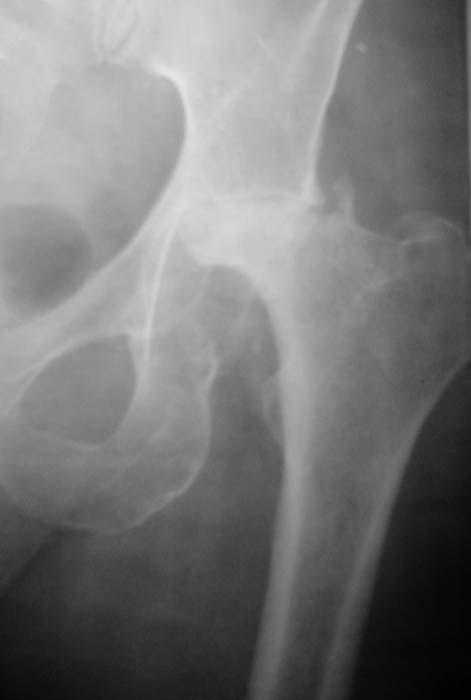

Уважаемые коллеги! Прошу Вас оказать консультативную помощь. Женщина, 44 года, инвалид 3 группыДиагноз: СКВ, асептический некроз головок обеих бедернных костей, двусторонний артроз 3-4 ст., болевой синдром, приводящая контрактураправого тазобедренного сустава, хронический волчаночный гепатит, спленомегалия, анемия, СКВ с 2002 года (подтверждена наличием lupus-клеток), получала специфическую терапию, медрол 16 мг/сут. Боли в левом тазобедренном суставе появились в сентябре 2003 года. Динамика отражена на рентгенограммах. В марте 2004 года - синдром Мэллори-Вейса, кровотечение остановлено эндоскопически. Объективно: кожа бледная, пастозность, отечность лица, высыпания на лице практически отсутствуют. Печень +6 см, селезенка не пальпируется. АД140/80, пульс 100, дыхание 15.

Ходит с тростью, хромота. Объем движений в суставах: справа - сгибание 90, разгибание 170, отведение 0, приведение 20, внутренняя ротация 15;слева - сгибание 90, разгибание 180, отведение 0, приведение 20, внутренняя ротация 0, наружная ротация 20. ЭКГ - отклонение ЭОС влево, гипертрофия левого желудочка, дистрофические изменения миокардаОбщий анализ крови: Э. 3,6, Hg 100, цп. 0,83, л.7,3, э.1, п.3, с.72, л.19, м.5, СОЭ 5 Общий анализ мочи: объем 120,0, уд.вес 1008, желтый, р-ция кислая, сахар/белок/цилиндры нет, эпителий и эритроциты единичные, Л.1-2, солиоксалатовые в небольшом к-ве. Биохимический анализ крови Билирубин 11,5 ммоль/л (прямой 0, непрямой 11,5), АСТ 0,24, АЛТ 0,61, протромбиновый индекс 100, рекальцификация 150, фибриноген 1,99,толерантность 8, фибринолитическая активность 240, общий белок 74,3, сиаловые кислоты 250 ед., С-реактивный белок 0. Пациентка желает выполнить тотальное эндопротезирование. Допустимо ли выполнение подобной операции? При каких условиях, дополнительной терапии? Особые предоперационные мероприятия? Личный опыт? Комментарии?Мнения? Заранее благодарю!!! С уважением, А.В.Владзимирский Донецкий НИИ травматологии и ортопедии